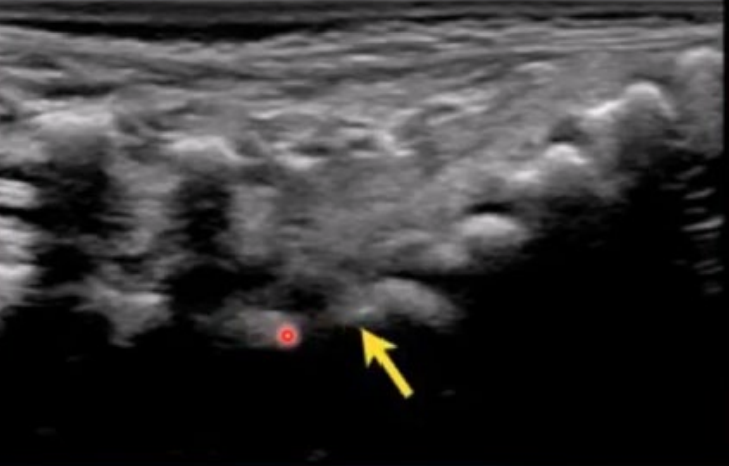

a

L1

b

L2

c

L3

d

L4

e

L5

f

S1

g

S2

h

S3

i

S4

J

S5

arrow

filum terminale

red arrow